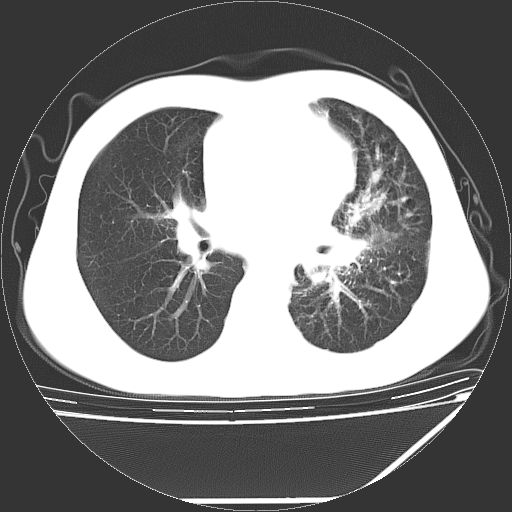

男,13岁,咳嗽、咳痰伴发热一周。

上纵隔课件多枚淋巴结,部分相互融合,左侧支气管壁增厚,肺纹理较右侧增粗,患者,男,13岁,

中上纵隔见多枚淋巴结肿大,部分相互融合成团片,左肺门增大,上叶支气管变窄,肺内多处斑片状 索条状及棉絮状致密影。临床“男,13岁,咳嗽、咳痰伴发热一周。”首先考虑:原发综合征!不除外淋巴瘤可能!

纵隔多发肿大淋巴结,部份有融合改变。双肺血管气管束增厚,以肺门为中心向外周散发,以左肺下叶为明显。考虑淋巴瘤可能性大。不除外原发综合征。

中上纵隔见多枚淋巴结肿大,部分相互融合成团片,左肺门增大,上叶支气管变窄,左肺支气管血管束增粗,可见磨玻璃样影。临床“男,13岁,咳嗽、咳痰伴发热一周。”首先考虑:淋巴瘤可能性大!